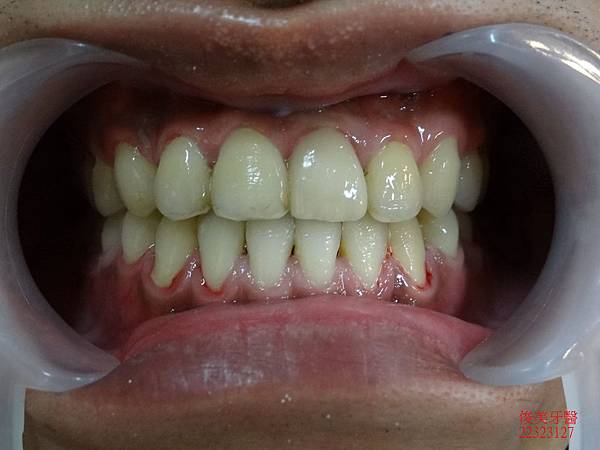

患者將以前做的假牙更換為全瓷牙冠,改善美觀問題。

做完超自然、完美,牙齦邊緣幾乎看不出來;全部療程在1年左右結束。

患者超級滿意。